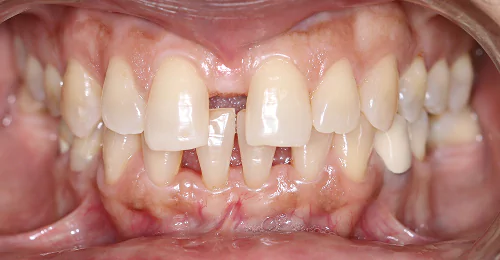

Orthodontic Case – II

(Case Done by Dr. Sonali Deshmukh M.D.S. / Orthodontist )

Correction Of Protruded

Small Lower Jaw

A child with protruded teeth and a small lower jaw at a young age can be treated by Myofunctional appliances which help in the growth of the jaw.

Pre Treatment

After Myofunctional appliances therapy for jaw growth accompanied by braces treatment for correction of protruded teeth.